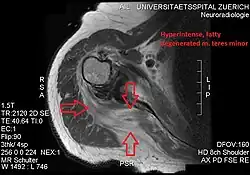

Atrophy of the teres minor muscle is often a consequence of a rotator cuff tear, but common isolated teres minor atrophies have also been found. A quadrangular space syndrome causes excessive and or chronically compression of the structures which pass through this anatomical tunnel. The axillary nerve and the posterior humeral circumflex artery pass through the space. People affected note shoulder pain and paresthesia down the arm first and foremost in abduction, extension, external rotation and overhead activity. Selective atrophy of the teres minor muscle has been seen and pulled together directly with compression of the corresponding axillary nerve branch or posterior humeral circumflex artery. Fibrous bands, cysts of the glenoid labrum, lipoma or dilated veins can occupy the quadrilateral space pathologically. Similar symptoms are common with anterior shoulder dislocation, humeral neck fracture, brachial plexus injury and thoracic outlet and inlet syndrome. It is important to include those pathologies for a complete as possible differential diagnosis.

Ultrasonography is a tool to detect a fatty degenerative atrophy of the teres minor and shows in affected muscles increased echogenicity and betimes a slight reduction in muscle bulk. MR imaging helps to consolidate the diagnosis of neurogenic muscle atrophy. Extracellular edema after traumatic events causing neural damage show an increased signal intensity on T2-weighted MRI sequences and normal intensity on T1-weighted sequences. Posterior humeral circumflex artery compression and reduced blood flow in stressful arm positions and or maneuvers can be diagnosed by a Doppler ultrasonography. The nerve should be detected adjacent to the vessel. In an elevated arm position the axillary neurovascular bundle can be seen at the posterior axillary fold just before it perforates the deltoideus, while the posterior course is well visible in the neutral position. For a detailed assessment of the artery, a MR angiography is required. The major task of an ultrasonographic examination is to rule out any space occupying mass. Additional electromyography is helpful to reveal any decelerated nerve conduction velocity, and thus denervation of the concerned muscle.[6]